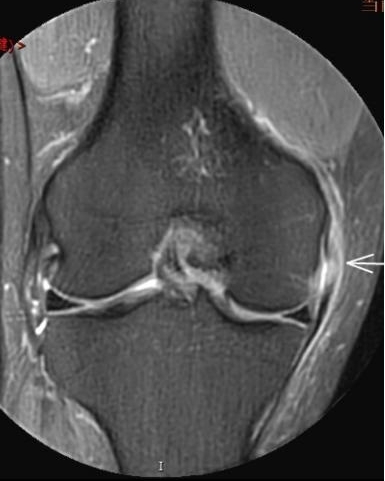

4. 不明腫脹+發(fā)熱——滑膜的“洪水警報”

場景:膝蓋腫成“發(fā)面饅頭”,皮膚發(fā)燙如“小火爐”

MRI偵查:鑒別痛風(fēng)性滑膜炎、感染或類風(fēng)濕病變,阻止“炎癥風(fēng)暴”

(滑膜增厚、積液)